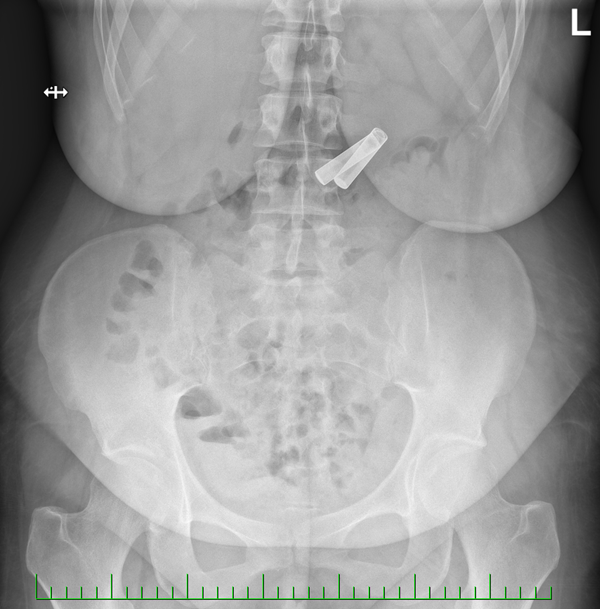

Dvě AA baterie. Tady máme kompletní příběh v chronologickém pořadí - pohled na rentgen, baterie v žaludku zachycená kličkou a obě vytažené baterie. Nešlo o jedinou extrakci baterií u této pacientky, ale v tomto případě na nás byla hodná. Při jiné příležitosti se jí podařilo jeden konec baterií rozdrtit (asi nohou od židle?) a tak byl nepravidelný a ostrý. Proč nám to trochu neztížit, že?